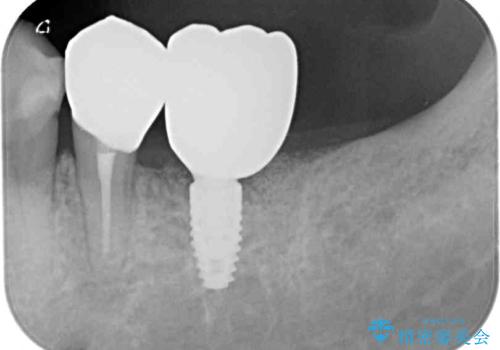

- 一度治療を終えたものの、奥歯へインプラントの追加を希望された患者様です。

最後臼歯部にインプラントを1本追加埋入し、2歯連結のクラウンにて補綴治療を行うこととしました。